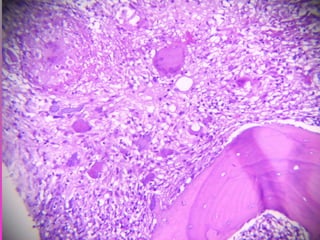

 SE RECIBE TEJIDO ÓSEO CON ABUNDANTE

MATERIAL DE ASPECTO CASEOSO,

FRIABLE CON UN VOLUMEN DE 2 CM. SE

INCLUYE LA TOTALIDAD DE LA MUESTRA

PARA SU ESTUDIO.

 TUBERCULOSIS ÓSEA ( MAL DE POTT )

 1. ACÚMULO DE NEUTRÓFILOS

 2. REEMPLAZO POR MACRÓFAGOS

 3. CÉLULAS EPITELIOIDES

 4. CÉLULAS DE LANGHANS

 5. LINFOCITOS

 6. NECROSIS CASEOSA

7. ABSCESOS FRÍOS

 8. HIPEREMIA

 9. OSTEOPOROSIS

 10. DESTRUCCIÓN ÓSEA Y NECROSIS

 COMPRESIÓN, COLAPSO Y DEFORMIDAD